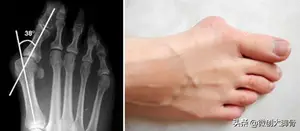

大脚骨如图,拇趾向二趾偏斜,并且大于15度,会逐年加重

1、我们把拇趾偏斜角度小于15度的叫生理性拇外翻,就是正常人几乎都有,拇趾偏斜角度超过15度叫病理性拇外翻,病理性拇外翻无疑问肯定是要治疗的,那生理拇外翻我们是有争议的。